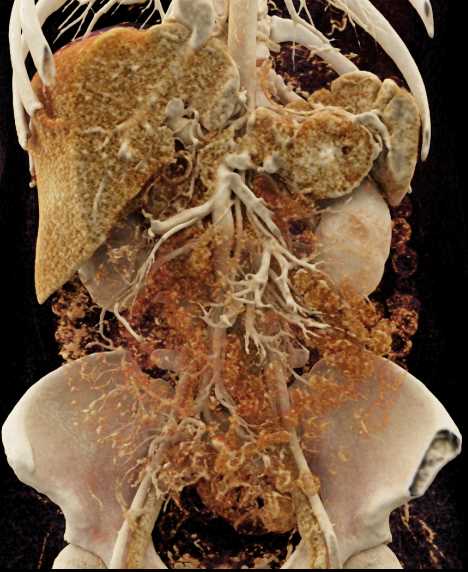

Neuroendocrine Tumor Pancreas